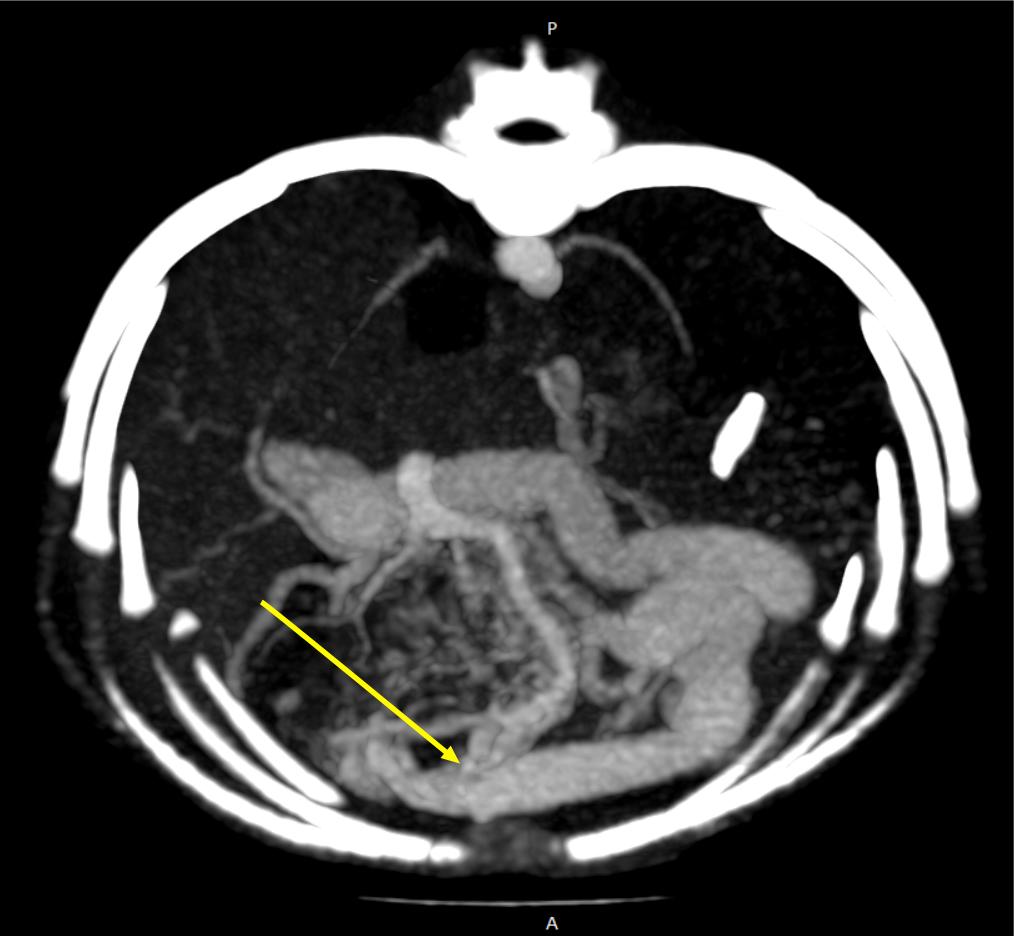

АВМ печени принято делить на правосторонние и левосторонние. Последние подразделяются на левую латеральную и медиальную мальформации в зависимости от положения выносящей вены (рис. 2).

Диагностика печеночных АВМ осуществляется с применением КТ-ангиографии, выявляющей сосудистую сеть (или «гнездо»), образованную ветвями приносящей печеночной, гастродуоденальной, левой желудочной и другими артериями, через которую происходит слияние с воротной веной (рис. 3). Артериальная фаза является самой важной в идентификации приносящих ветвей артериовенозной мальформации. АВМ имеют тенденцию изменяться со временем, в связи с этим КТ-ангиографию рекомендуют проводить как можно ближе к дате планируемого хирургического вмешательства.